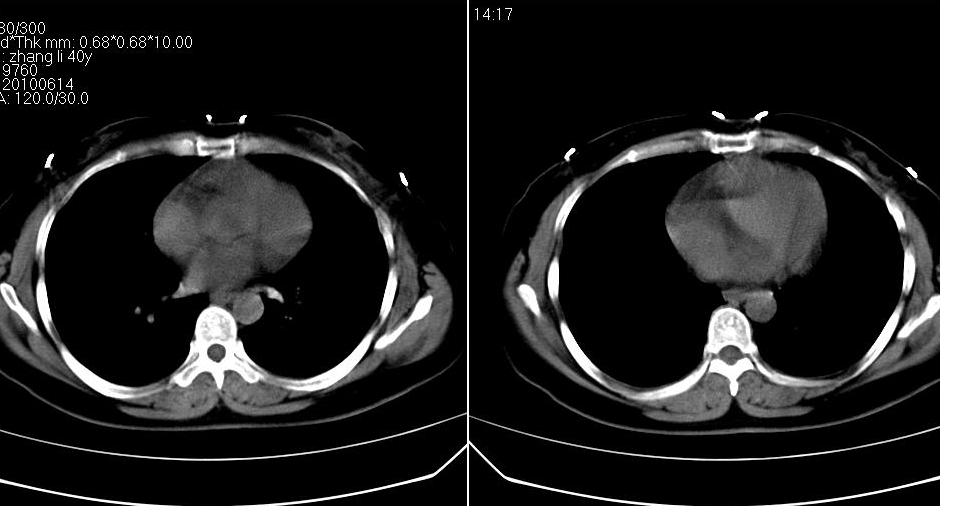

女 40岁,胸片体检发现右肺肿块,无任何症状。

下叶背段多发性小腺泡结节,考虑结核。

肺动静脉瘘可考虑,建议增强

考虑右肺下叶背段继发性肺结核。